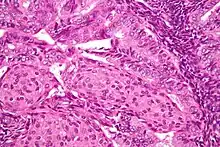

Image of the histology of an endometrioid endometrial adenocarcinoma

Endometrioid endometrial adenocarcinoma—very high magnification—H&E stain